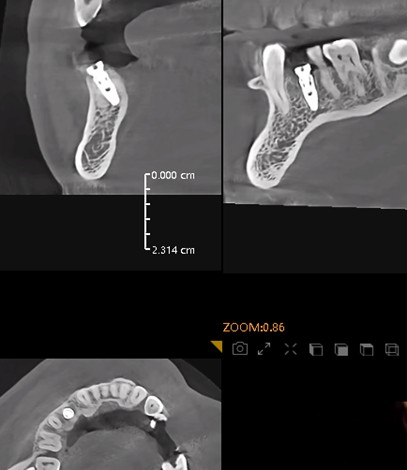

Postoperative CT scans and intraoral photographs were obtained.

November 23, 2025: Implant follow-up examination. The implant surgical site showed excellent healing, with no abnormal bone density around the implant and satisfactory osteogenesis. The third-stage impression taking was implemented. The panoramic radiograph below confirmed the complete seating of the implant impression coping.